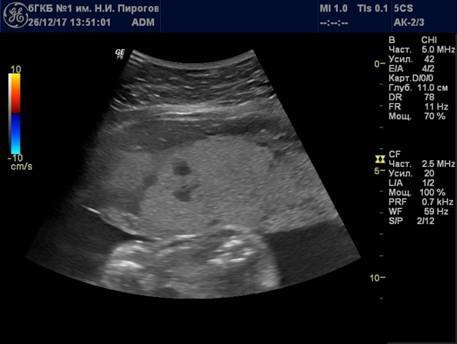

Выявляемые при серошкальном исследовании плаценты ан- или гипоэхогенные зоны чаще всего являются эхографическими срезами участков расширения ее МВП (Рис. 7) и значительно реже сосудов плода (Рис. 8). Расширение МВП может быть связано как с поступлением материнской артериальной крови, и отражать одно из состояний артериального капиллярного русла маточно-плацентарного кровотока (Рис. 9), так и с оттоком в материнское русло венозной крови (Рис. 10). При этом направление тока крови может быть установлено при цветовом допплеровском картировании (ЦДК). Следует иметь в виду, что венозное звено маточно-плацентарного кровообращения состоит из двух функциональных частей: венозных коллекторов плацентарного ложа возле разделительных септ и краевых синусов [10], которые также могут быть расширены (Рис. 11).

Рис. 7. Беременность 33 нед. Участок расширения межворсинкового пространства.